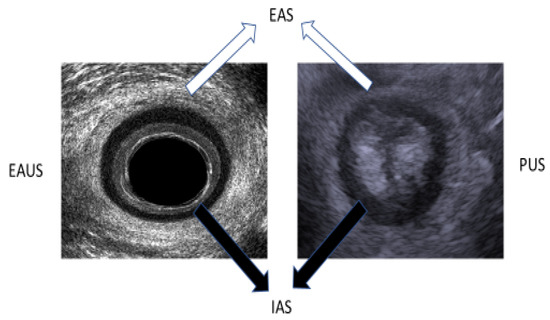

The examination was performed with a transrectal ultrasound using a 360° endoanal probe with three-dimensional (3D) anorectal reconstruction (BK Ultrasound, Peabody, MA, USA) after the performance of a cleansing enema. The examination was performed while the patient was lying in the left lateral position at rest. The ultrasound probe was inserted to the rectum at a depth of 10 cm, and then withdrawn to the level of the anal canal, where the examination of the anal muscular apparatus integrity was performed. Afterward, a 3D reconstruction of the anal canal was performed automatically. The integrity of the puborectalis muscle was measured in the upper anal canal, whereas that of the internal anal sphincter (IAS) and the external anal sphincter (EAS) was measured in the mid-anal canal (Figure 1). Defects in the IAS were defined as hyperechoic (white/gray) echo structures in the internal anal sphincter ring. Defects in the external anal sphincter were defined as hypoechoic (black) echo structures in the external anal sphincter ring (Figure 2).

Figure 1.

Mid-anal canal image in EAUS (left image) and axial view on PUS (right image). EAS—external anal sphincter. IAS—internal anal sphincter.

TPUS was conducted using 5–7.5 MHz end-fire transducer or curvilinear 3.5–6 MHz (B&K, 3000, Peabody, MA, USA) probes after liberal application of acoustic gel to the perineum. The examination was performed while the patient was lying in the left lateral position at rest. The examination was performed with the transducer initially applied transversely to the perineal body or the perianal area in order to identify the axial view of the anus using as a landmark the hypo-echoic ring of the internal anal sphincter (Figure 1). The transducer was then turned 180° to obtain a sagittal view of the rectum with extension of the hypoechoic internal anal sphincter appearing above and below the anal canal in profile. The anorectal junction was clearly seen with the bright hyperechoic elliptical bundle of the puborectalis sling. Defects in the internal anal sphincter were defined as hyperechoic (white/gray) echo structures in the internal anal sphincter ring. Defects in the external anal sphincter were defined as hypoechoic (black) echo structures in the external anal sphincter ring (Figure 2).